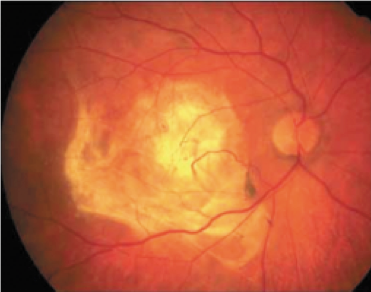

Le alterazioni sopra descritte rappresentano una situazione di rischio perché si sviluppino al di sotto della retina dei nuovi vasi sanguigni (neovasi) con l’intento di portare nuovi nutrienti e nuovo ossigeno alla retina in difficoltà. Questi neovasi però sono alla base dell’evoluzione umida (neovascolare) della DMS poiché avendo pareti fenestrate (non continenti) perdono liquidi e/o sangue e infiltrandosi nello spessore della retina ne distruggono l’architettura. Rispetto alla forma secca il processo neovascolare-essudativo è rapidamente ingravescente e si conclude con la formazione di un’ampia cicatrice maculare in cui i fotorecettori risultano distrutti. A questo punto la visione centrale è gravemente e irrimediabilmente compromessa. La forma umida è responsabile dell’80% dei casi di cecità legale da degenerazione maculare.

A sinistra e al centro: forma umida della degenerazione maculare senile con emorragia maculare. A destra: stadio finale con cicatrizzazione della macula (maculopatia disciforme)